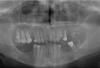

Mirina Опубликовано 30 марта, 2011 Поделиться Опубликовано 30 марта, 2011 Уважаемые стоматологи, обращаюсь к Вам за советом по вопросу удаления кисты на верхнем втором зубе, на прикрепленной ортопантомограмме слева. Дело в том, что этот зуб восстановлен на штифту и у него была сделана резекция корня. Есть ли в этом случае варианты и, если да, то какой предпочтителен?Заранее спасибо за участие. Ссылка на комментарий